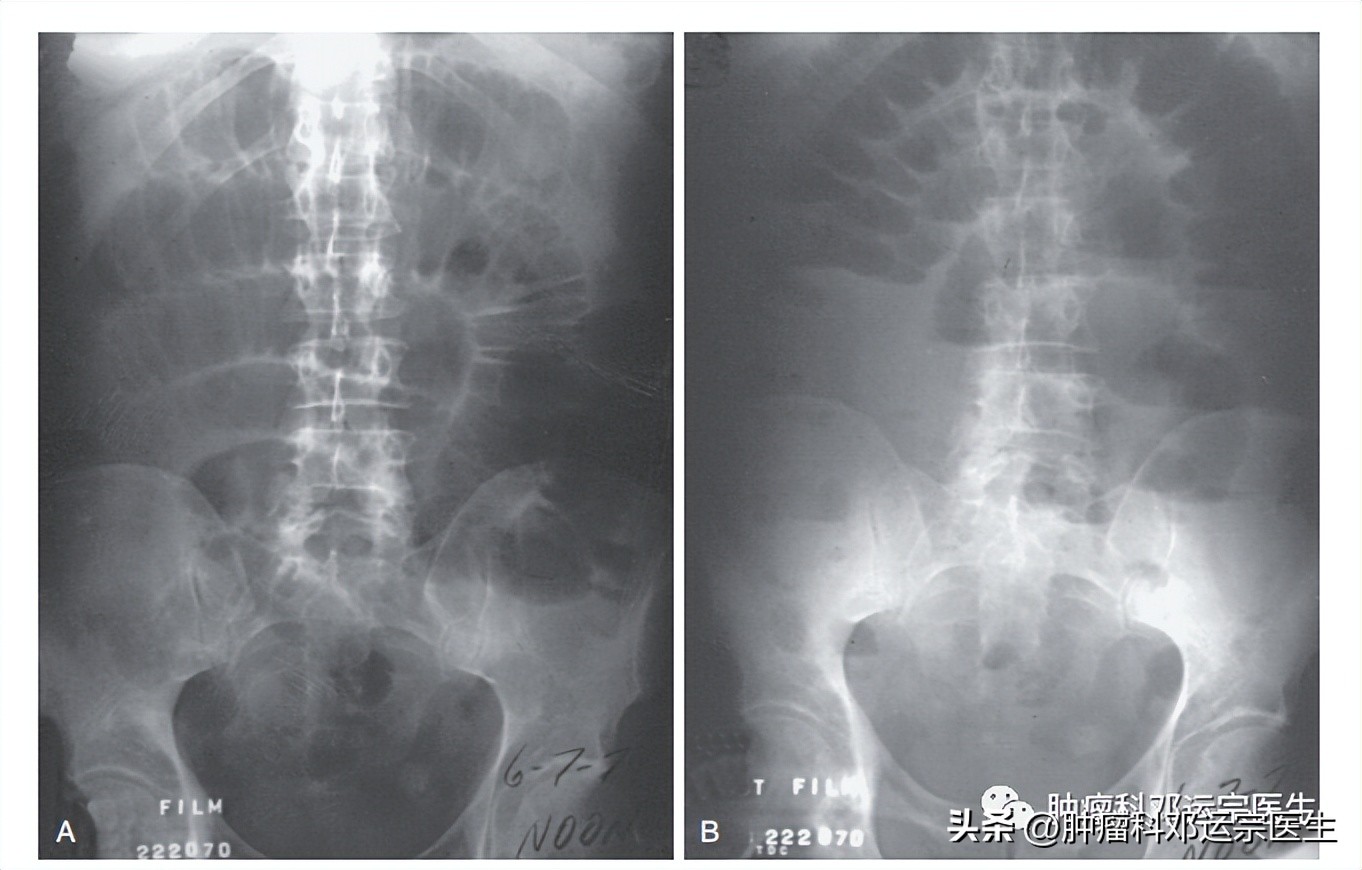

共识10:推荐腹部X光平片检查作为初步诊断

在有限条件下,X光平片虽然价值有限,但也是有必要进行的。在更为复杂的梗阻中,多气液平、小肠袢扩张和结肠无气体显影是小肠梗阻的主要症状,但X线平片的总体敏感性和特异性较低(敏感性约70%) [8, 9]。小肠梗阻中肠穿孔继发的大量气腹也能够在直立位的X线平片上观察到。但是,X光平片不能够早期发现腹膜炎或者肠坏死等迹象[10]。另外,腹部X光平片提供的信息价值有限,不能帮助我们进一步了解各种肠梗阻的解剖信息。